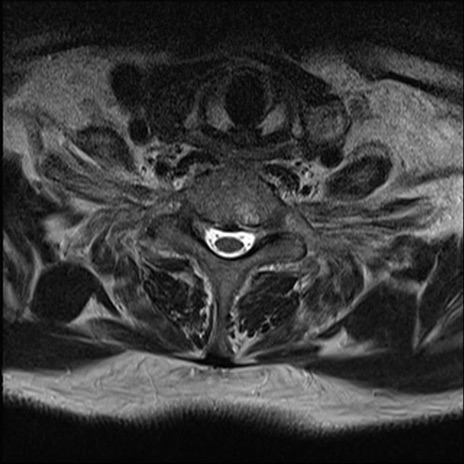

【整形】TIPS症例7 頚椎MRI T2WI(横断像)

頚椎MRI

矢状断像と横断像